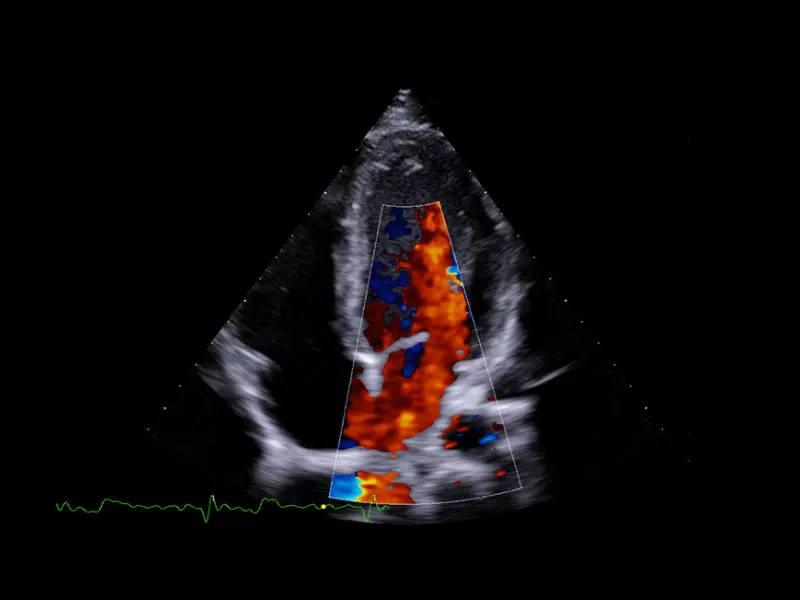

MyLab™9 Platform - Ultra-sensitivity Colour Doppler for precise visualization pulmonary veins

MyLab™9 Platform - Ultra-sensitivity Colour Doppler for precise visualization pulmonary veins